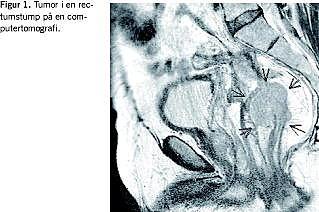

Morbus Crohn (CD) og colitis ulcerosa (UC) er sygdomme, der indebærer risiko for udvikling af dysplasi og kolorektal cancer (CRC), specielt ved tidlig sygdomsdebut og udbredt sygdom [1]. Der har derfor været tradition for rutinemæssig kontrolkoloskopi af disse patientkategorier. Til gengæld findes der ingen retningslinjer for kontrol af rectumstumpen hos disse patienter, når de er kolektomerede (Figur 1 ). Vi rapporterer om to tilfælde af CRC opstået i rectumstumpen hos en langvarigt syg CD- og en ligeledes langvarigt syg UC- patient.

I. En 59-årig mand, der var blevet kolektomeret 30 år tidligere for UC med anlæggelse af ileostomi og efterladelse af en rectumstump, blev henvist på grund af nytilkommen slimafgang per anum som eneste symptom. Han syntes ikke at være blevet rutinemæssigt undersøgt endoskopisk efter kolektomien. Udredningen var langvarig og vanskeliggjort af en fibrøs striktur 10 cm oppe, hvilket forårsagede kraftige smerter ved forsøg på rektoskopi. Ved computertomografi (CT) og rektoskopi i universal anæstesi (UA) med dilatation af strikturen fandt man en tumor oralt for med en biopsi, der viste adenokarcinom. Der påvistes desuden lungemestataser, hvorefter patienten blev henvist til onkologisk stråle- og kemoterapi; mors indtrådte fem måneder senere.